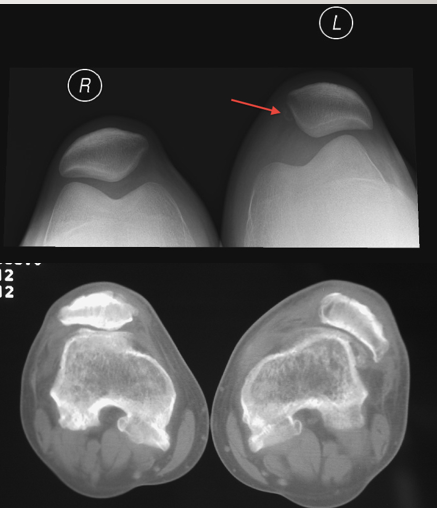

9

Q

Knee: Bipartite Patella

etiology anf complaints

A

Etiology: lack of fusion of patella at growth area; results in patella that is in multiple pieces

Typically, only hurts if there is repetitive trauma but patient cannot recall a specific injury

Incidental finding on radiograph

Common symptoms/ complaints:

Typically, asymptomatic

Sometimes pain resulting from trauma

10

PE and tests

Physical Exam:

TTP over patella if inflamed; otherwise, unremarkable

Tests:

X-rays: edges will often not be as sharp as fractures

MRI can help to visualize inflammation

11

Tx and pearls

Treatment:

Rest

Immobilization

Physical Therapy

Sometimes fixation is needed (treat it like a fracture)

Pearls:

Bilateral in 50% of patients with the disease